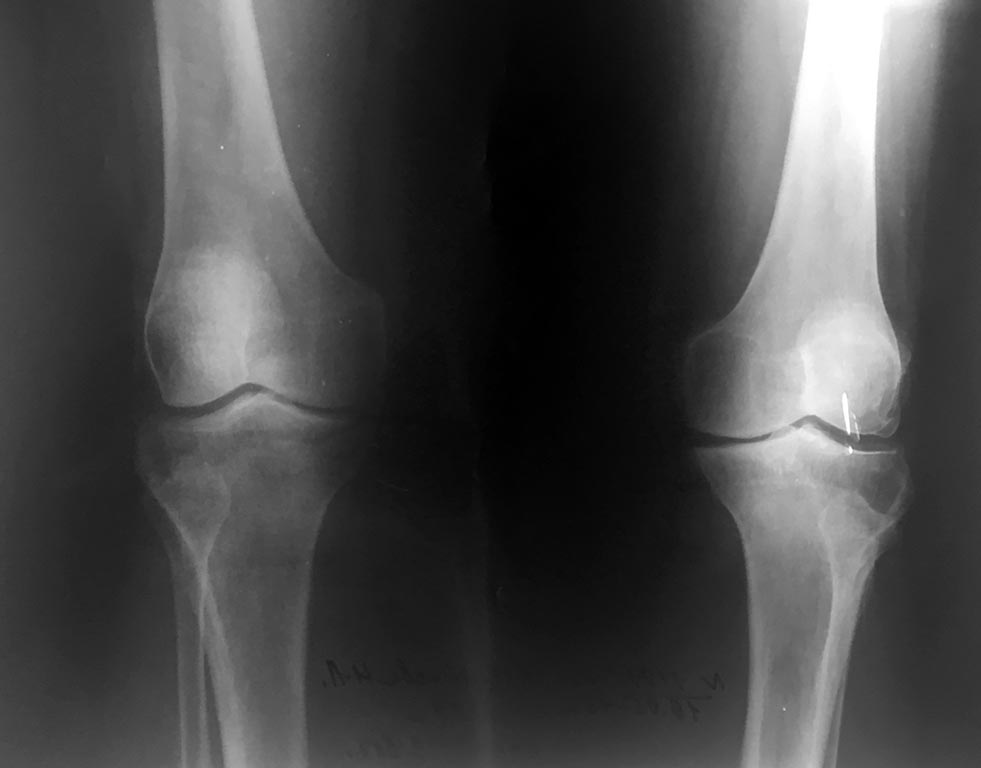

Пациентка 67 лет. Страдает двусторонним гонартрозом 2 ст.В течении

последнего года усилился и постоянно беспокоит болевой синдром. Варусная

деформация выражено умеренно.

Объём движений 180-85 гр. Без значимой сопутствующей соматической

патологии.Консервативное лечение с малым эффектом. Какие варианты

лечения в этом случае приемлемы? Возможна ли в данном случая

корригирующая остеотомия ББК ? или показано эндопротезирование?

одномыщелковое? Спасибо за ответы!